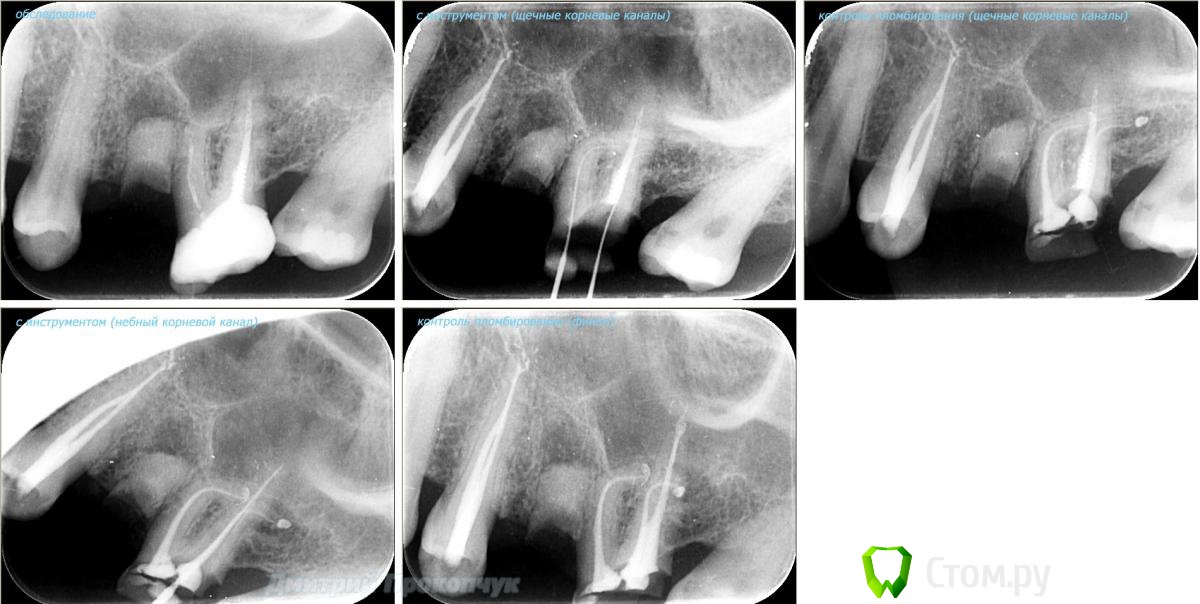

punkrat Опубликовано 16 сентября, 2014 Поделиться Опубликовано 16 сентября, 2014 Коллеги, тема , возможно, не имеет смысла просто приятная мне эндодонтия, сохранил с предыдущего места работы. Да, будь я проклят, я все знаю, НИГДЕ НЕТ КОФЕРА, на новом месте с этим норм. В общем если посчитаете, что я недостоин постить тут свои снимки, то так тому и быть, удалю тему.. 01. плановый ретрит 46ого и результат через 7 месяцев. Осложняющим моментом тут было то, что длина каналов была около 26 мм... 02. первичное эндо 34 (подготовка к ортопедии) + бонус - ретрит 35 03. ретрит 26 (подготовка к ортопедии) 04. ретрит 15, 16 (подготовка к ортопедии). основная сложность была в ретрите 15 - он был запломбирован термафилами, да еще снабжен свш... 05. ретрит 27 (подготовка к ортопедии). Ничего особенного, со временем посмотрим какова будет убыль этого совсем немаленького разрежения 06. ретрит 13. Разумеется пришлось выбивать вкладку, а потом еще попилить 3-4 миллиметра цемента, но, таки попилил куда нужно... 07. ретрит 17 (подготовка к ортопедии). В данном случае я, кажется, потратил больше времени на снятие литого моста, чем на лечение 17)) 08. ретрит 16 (подготовка к ортопедии). Снимка с инструментом нету, поскольку, визиограф сломался и его делал на пленку. 15 разумеется тоже перелечен... 09. плановый ретрит 16 10. первичное эндо 36, рядовой случай что дистальный щечный удалось найти не сразу, он был спрятан под нависающим дентиклем 11. ретрит 12, 11 (подготовка к ортопедии). Казалось бы, рядовой случай, если бы корневые каналы обоих зубов не были бы налухо забиты резорцин-формалиновой смесью... 12. ребенок 9ти лет, острый пульпит 46, попробовал оставить витальным. Пока полет нормальный, но даже если придется делать эндо в последствии, лучше когда оно будет сделано в более старшем возрасте... 13 Ссылка на комментарий